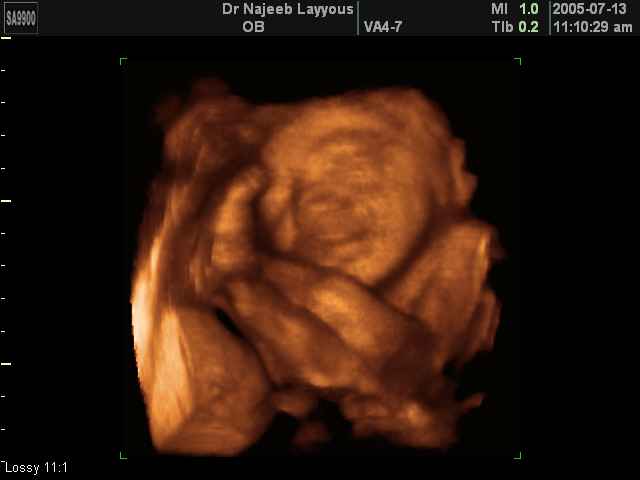

صور لتصرفات الجنين داخل الرحم بجهاز الالتراساوند ثلاثي الأبعاد | الدكتور نجيب ليوس

صور بجهاز الموجات فوق صوتية ثلاثي الأبعاد لتصرفات الجنين داخل الرحم